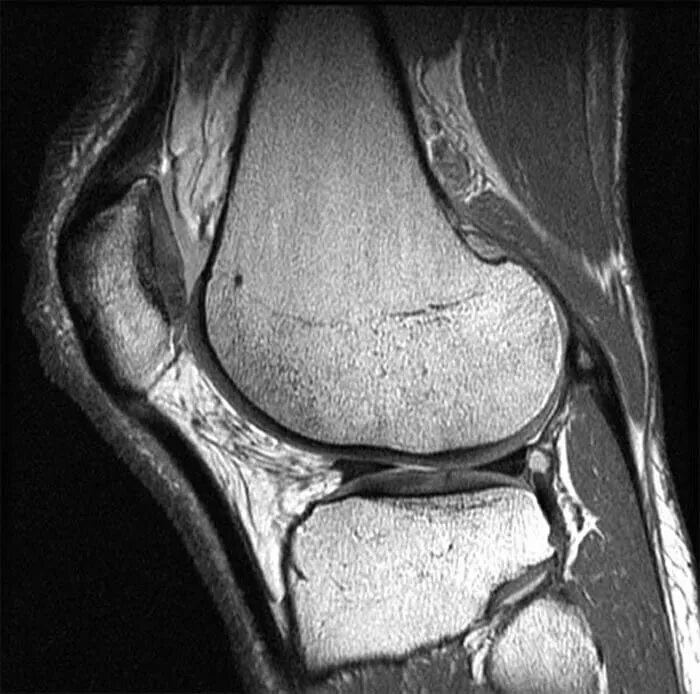

Мрт коленного сустава времени